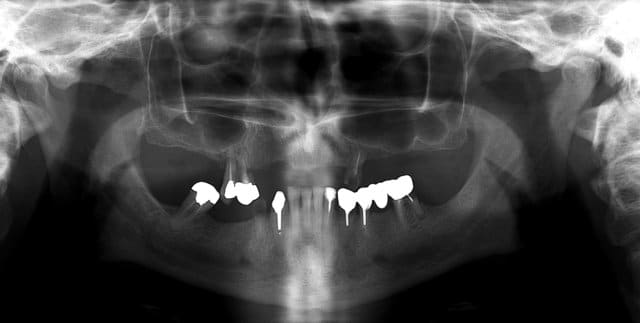

extraction: 14-15-23-44 et 36 (ou amputation, mais à quoi bon ?)

reprendre la courbe occlusal avec des céram sur 43-46-33-34

bridge sur implant sur 44 -46 et 35-36 (ou 35-37?)

complet haut amovible sur deux barres (donc 4 implants en haut) ou sur 4 locators (y en a qui ont déjà fait ?)